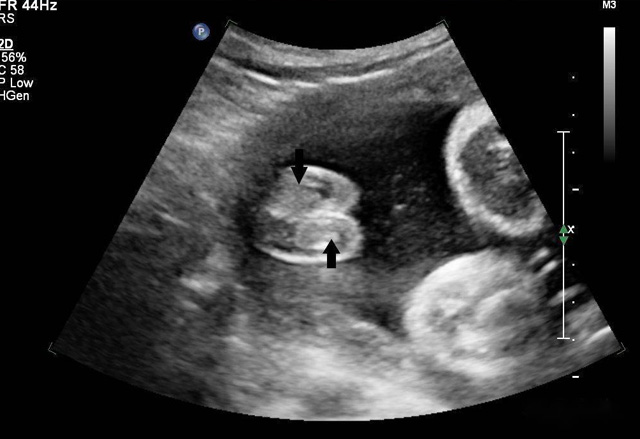

動態(tài)三維超聲成像有時間因素(心動周期)三維超聲成像分為靜態(tài)三維超聲成像和動態(tài)三維超聲成像,整體成像法重建感區(qū)域實時活動的三維圖像,稱為四維超聲心動。

三維超聲技術可用于心臟、腹腔、婦科、產科、小器官、血栓、血管成像等多方面。